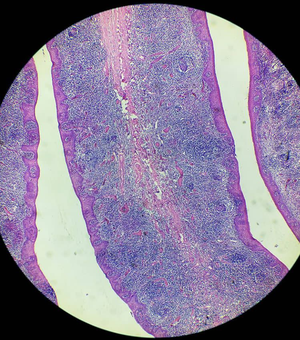

Histology 💙

Histology

Spleen